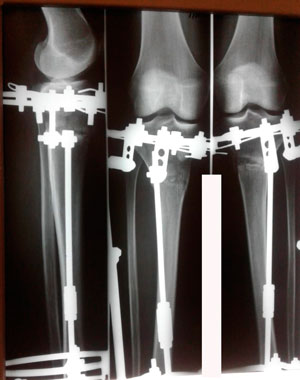

Пациентка - 37 лет.

Диагноз: варусная деформация голеней. Ротация с обеих сторон.

Дата операции - 24.10.2019г.